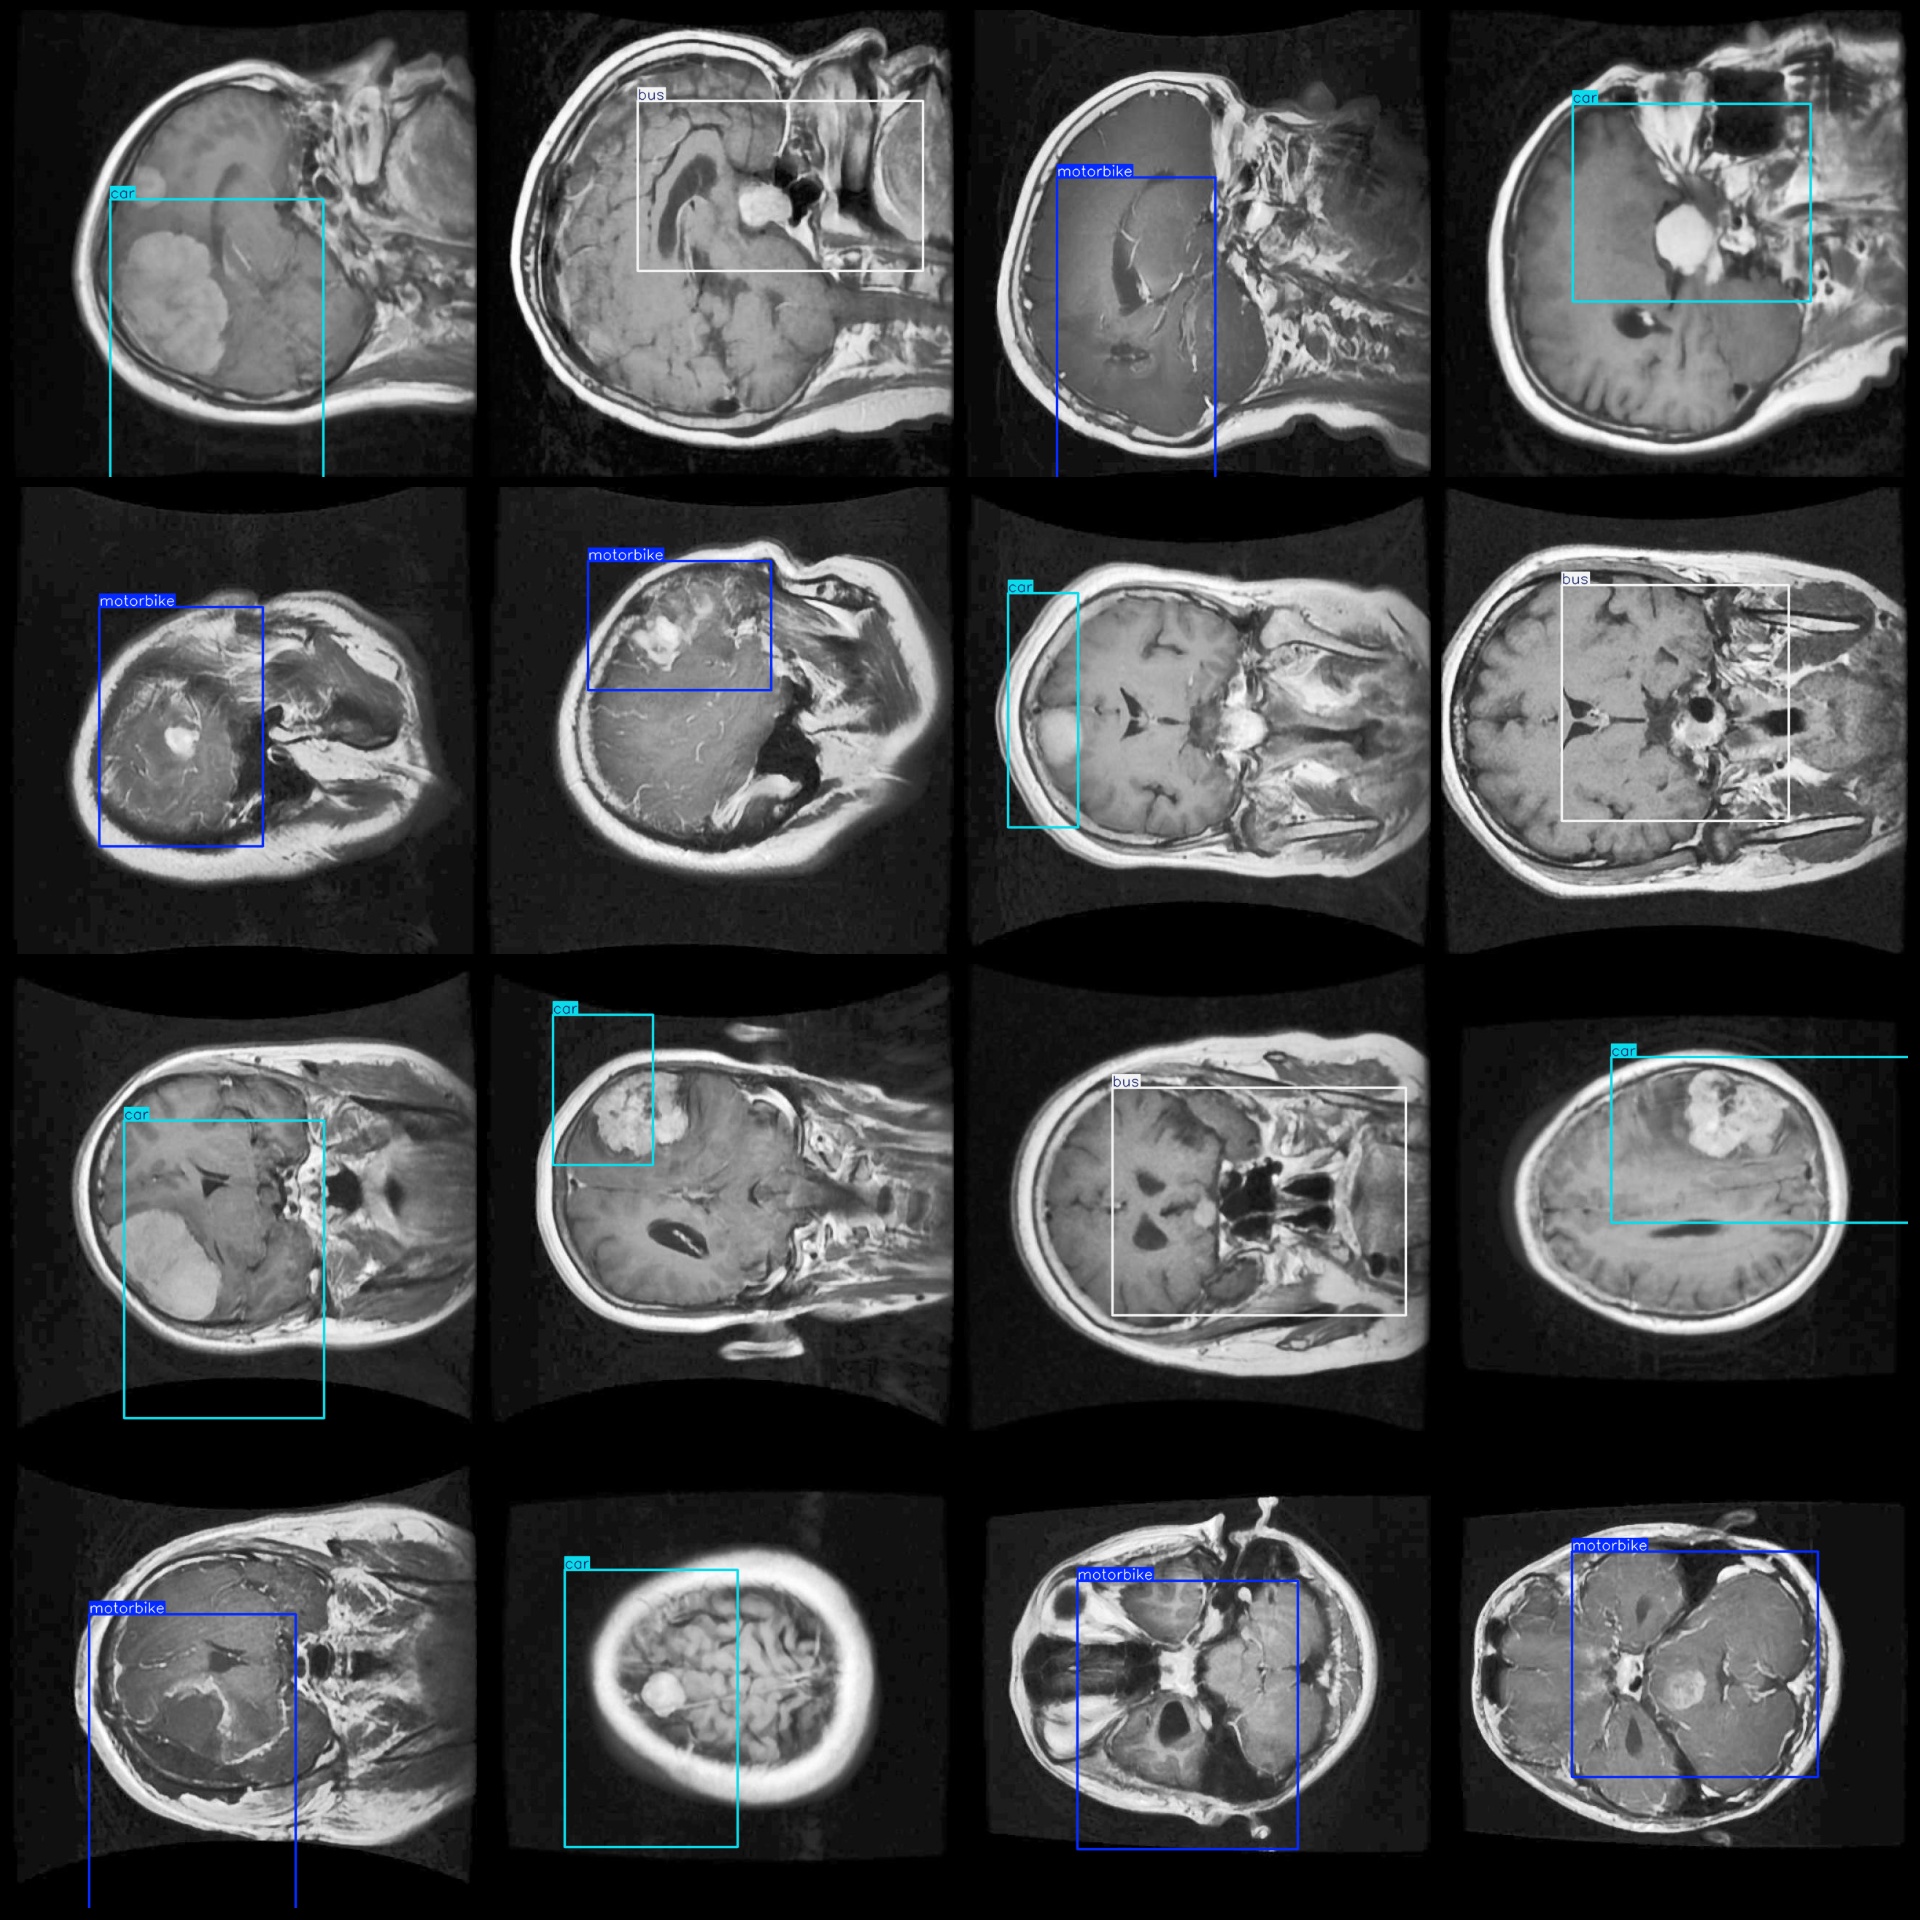

标注例子:

【模型可以检测出3类别】

'Glioma', 'Meningioma', 'Pituitary tumor'